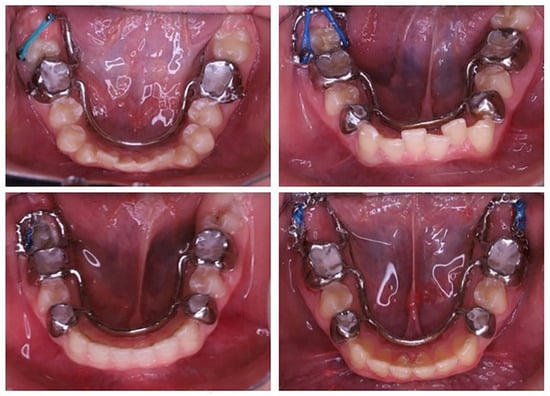

Figure 5. Representative clinical cases treated with customized PDaA systems.

The PDaA system is cemented intraorally using a glass-ionomer cement (GIC), which tolerates a slightly moist field. Upon removal of the surgical dressing, minor exudate is common and may compromise the adhesion of resin-based cements, hence the preference for GIC. The elastomeric element is attached to the extended arm using various techniques Figure 5, such as an elastomeric ligature with an auxiliary stainless-steel ligature or direct application of an elastomeric chain (single or double strands). As the MM2 is displaced, the elastomeric element is either replaced with a shorter one or the point of attachment is moved to a more distal location along the cantilever.

Placement of a button on the impacted mandibular second molar and activation of an elastic traction element. The traction vector can be modified by attaching the elastic chain to various segments of the metallic extension of the PDaA.

The traction and uprighting of impacted mandibular molars require controlled, light to moderate orthodontic forces to ensure safe and effective tooth movement without causing damage to the surrounding tissues. The uprighting procedure is typically performed using light forces in the range of 50–80 g. These forces can be generated by stretching an elastic continuous chain by 25% to 50%, depending on the material from which the chain is made. Manufacturers usually provide force values for their chains when stretched to a specific extent, most commonly at 25% elongation. However, the most reliable method for determining the applied force is by using a force gauge. In our clinical protocol, we apply the chain stretched to 25%. The greatest amount of force is generated and perceived by the patient within the first 24 hours, after which a gradual decrease in force occurs.